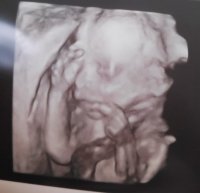

Absolutely beautiful xAmazing how quickly they progress at this stage. Molly malone hope your sickness easies off. I still get pangs of it as well and didn’t think it lasted this long with Elsie. Usually at night and can feel so uncomfortable already. My scan showed I have an anterior placenta so hopefully it moves. How is everyone else doing? X

View attachment 1070970 View attachment 1070972

too. All was fine although madam was very lazy haha. After 3 attempts she got all her measurements and all seemed well. Under consultant care with further scans booked for 28, 32 and 36 weeks with a view to be induced at 39 weeks. Bit gutted as wanted a boy but it is what it is. She’s healthy and that’s what matters.

too. All was fine although madam was very lazy haha. After 3 attempts she got all her measurements and all seemed well. Under consultant care with further scans booked for 28, 32 and 36 weeks with a view to be induced at 39 weeks. Bit gutted as wanted a boy but it is what it is. She’s healthy and that’s what matters.